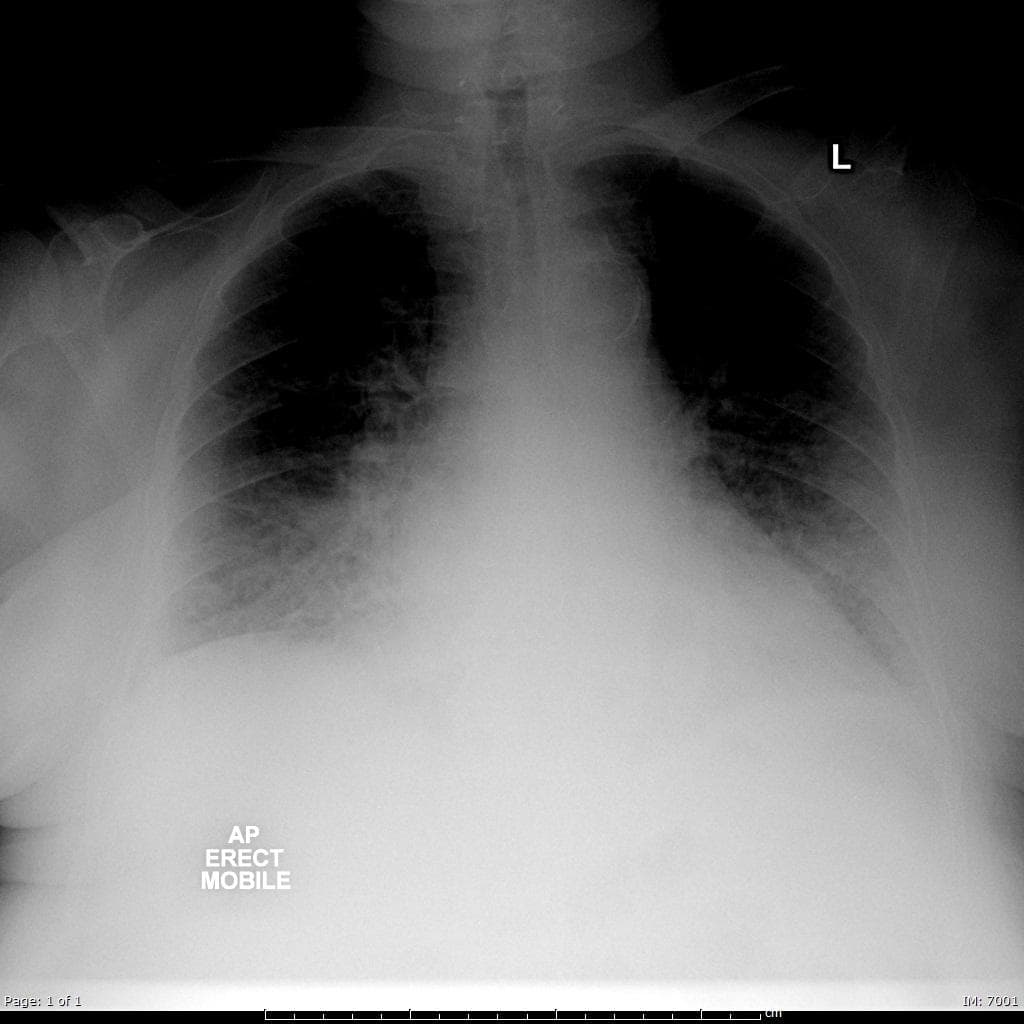

Nghi ngờ phình thất và vỡ thất được kiểm soát trên siêu âm tim qua thành ngực.

- Không thấy hình ảnh (no evidence of) vỡ thất, nhưng hình ảnh động (cine images) cho thấy thành trước giữa thất trái bị rối loạn vận động (dyskinetic), phồng ra ngoài trong thì tâm thu.

- Có tràn dịch màng ngoài tim lượng nhỏ (small pericardial effusion).

- Siêu âm tim qua thành ngực lặp lại sau 4 tuần cho thấy thành trước rối loạn vận động đã hồi phục, tràn dịch màng ngoài tim (pericardial effusion) đã biến mất, đồng thời phân suất tống máu cải thiện.